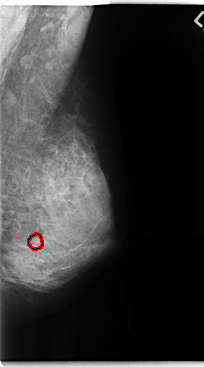

C_0257_1.LEFT_MLO

FILE: C_0257_1.LEFT_MLO.OVERLAY

TOTAL_ABNORMALITIES 1

ABNORMALITY 1

LESION_TYPE CALCIFICATION TYPE ROUND_AND_REGULAR DISTRIBUTION CLUSTERED

ASSESSMENT 3

SUBTLETY 5

PATHOLOGY BENIGN

TOTAL_OUTLINES 1

BOUNDARY